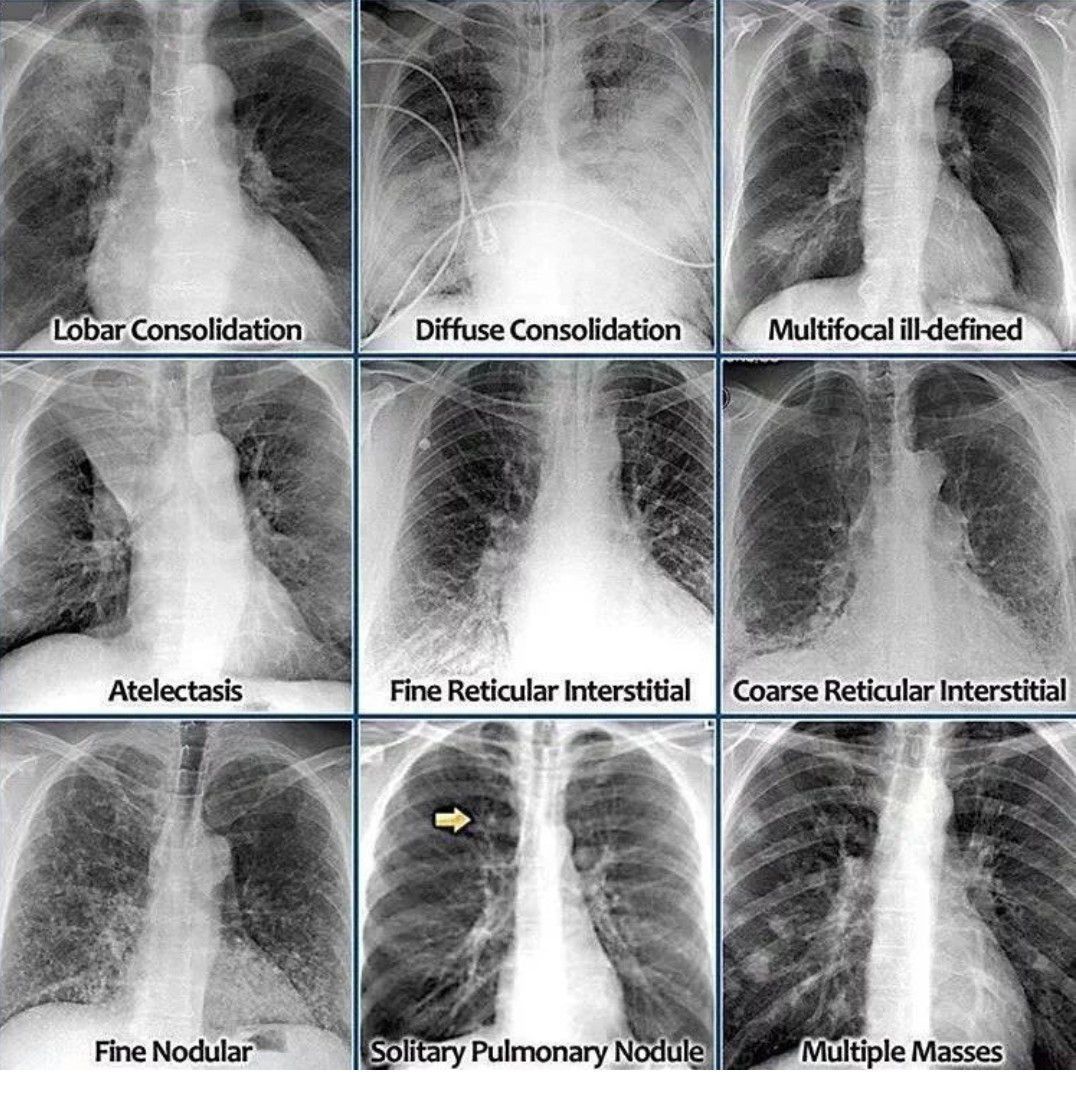

Chest X-ray

Here is a radiographical review of multiple chest conditions.